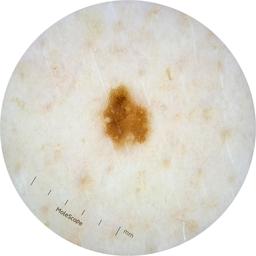

ISIC_2261268

2061 x 2061

acquisition_day 307

age_approx 50

anatom_site_1 Trunk

anatom_site_2 Posterior trunk

anatom_site_general posterior torso

diagnosis_1 Benign

diagnosis_confirm_type single image expert consensus

image_type dermoscopic